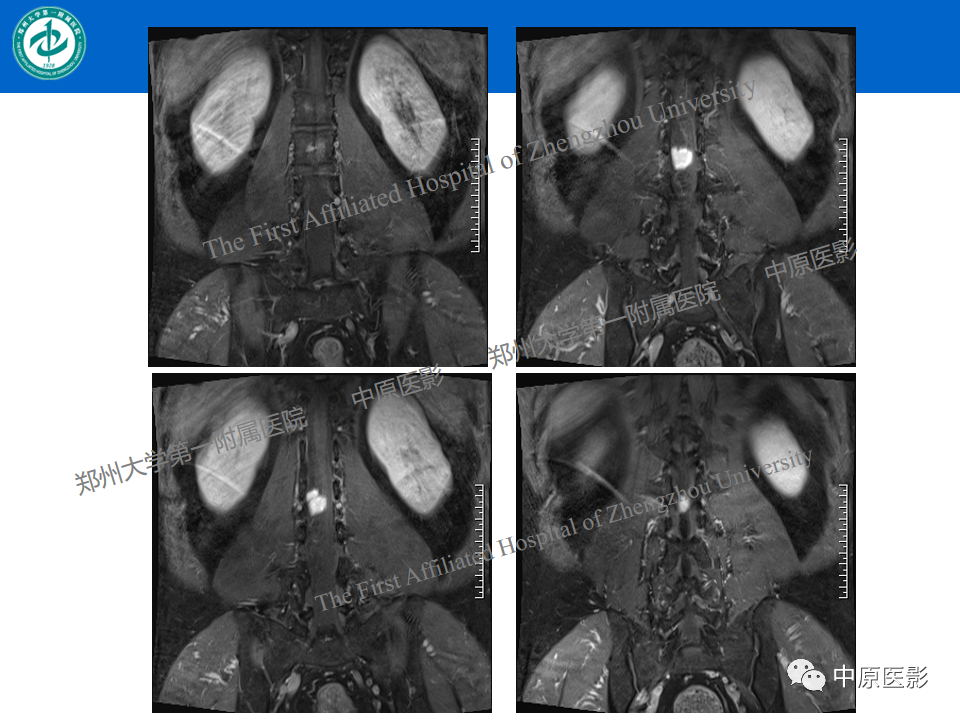

【病例】腰椎毛细血管瘤1例MR影像-5

【病例】腰椎毛细血管瘤1例MR影像-6

【病例】腰椎毛细血管瘤1例MR影像-7

【病例】腰椎毛细血管瘤1例MR影像-8